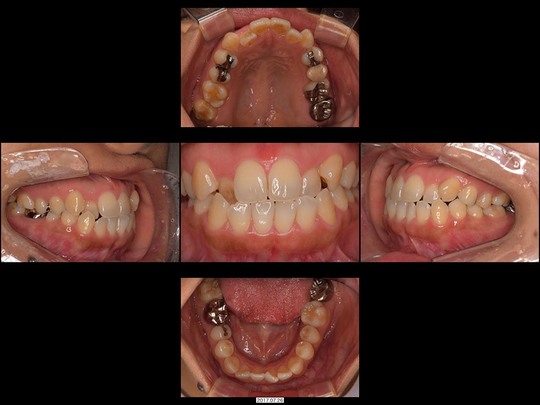

Eさん 30代 女性

矯正前

画像をクリックで拡大

矯正後

治療の説明

非抜歯にて、上の前歯だけワイヤー矯正しました。歯が移動できるスペースを確保するためにディスキング(歯の形を整える)しています。

治療の期間・回数

10か月、12回

​費用

470,800円